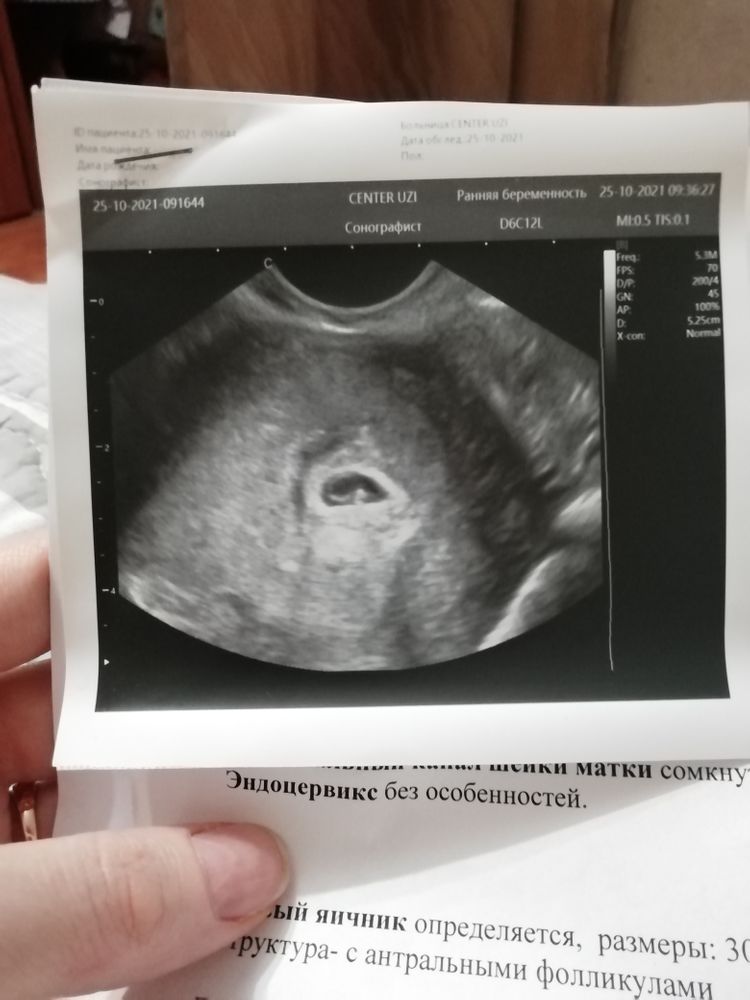

У меня тесты полосатятся как 4 недели и по узи ставят 4 недели(5я). Разве на 4х неделях аккушерских уже виден эмбрион и сердцебиение? По месячным если считать то это эмбриональных 4 а аккушерских 6...у меня взрыв мозга

Вам эмбриональный срок поставили по УЗИ, акушерских 6,в 4 акушерских и пя не видно по УЗИ,не то что эмбрион,ваше УЗИ соответствует вашему сроку